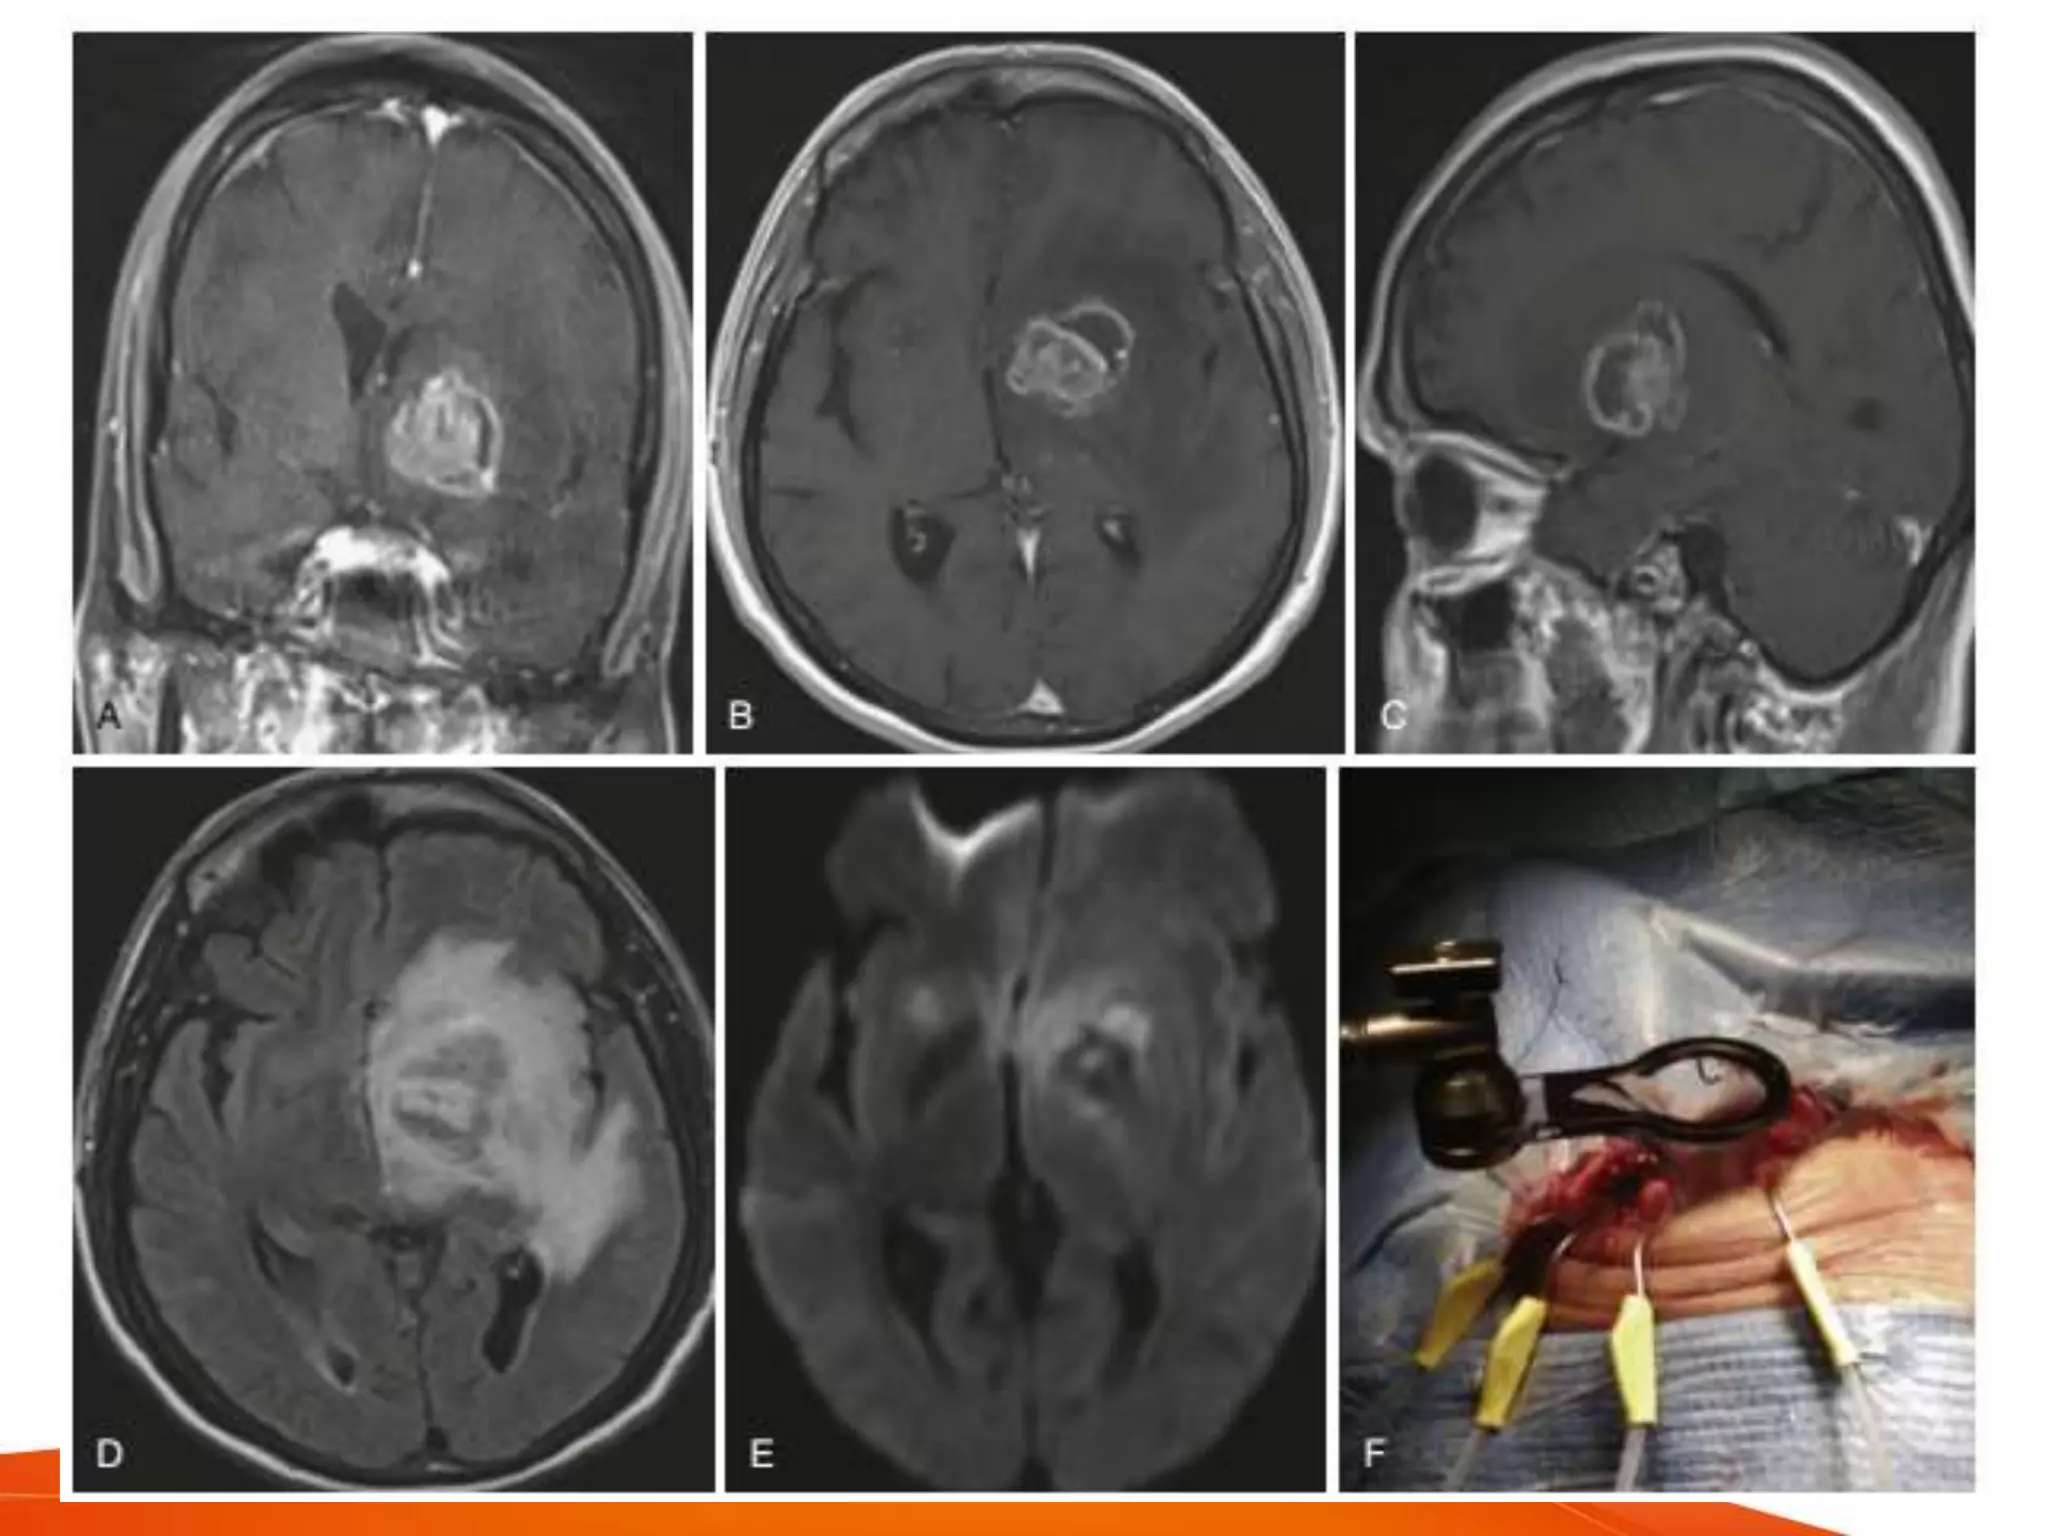

ASPIRATION

• provides specimens

• low surgery related morbidity and mortality

• post aspiration recurrence - upto 32%

• CT guided aspiration accurate within a few

mm with yield of 95%

• highly effective in definitive drainage of

abscess

• preferred treatment for deep seated

lesions or eloquent areas

• suitable for

– brain stem

– thalamus

– basal ganglia

• stereotactic drainage - can drain multiple

abscesses, with prolonged medical

therapy is effective

• frameless neuronavigation - best

technique to localise

• less chance of seizures and other

sequelae

• Ultrasound guidance

– real time

– reliable

– fewer risks

– minimally invasive and accurate

• other methods

– endoscoic stereotactic aspiration and

irrigation

• precise localisation, minimal craniotomy, multiple

lesions addressed